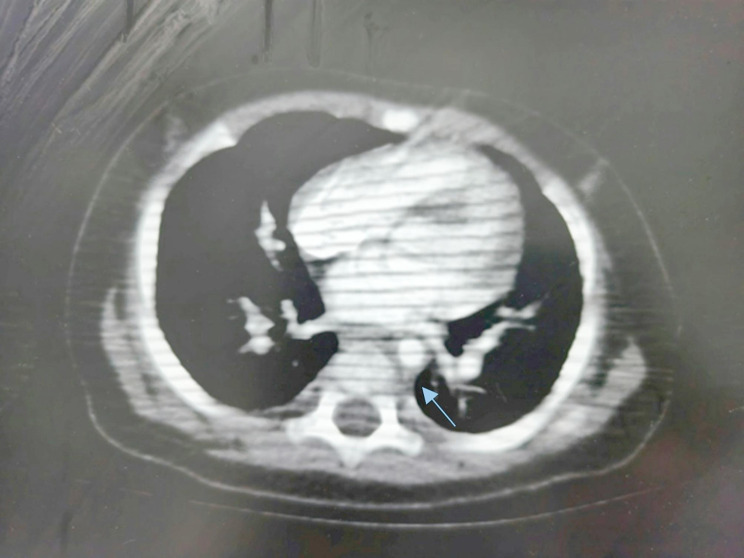

Abstract Image